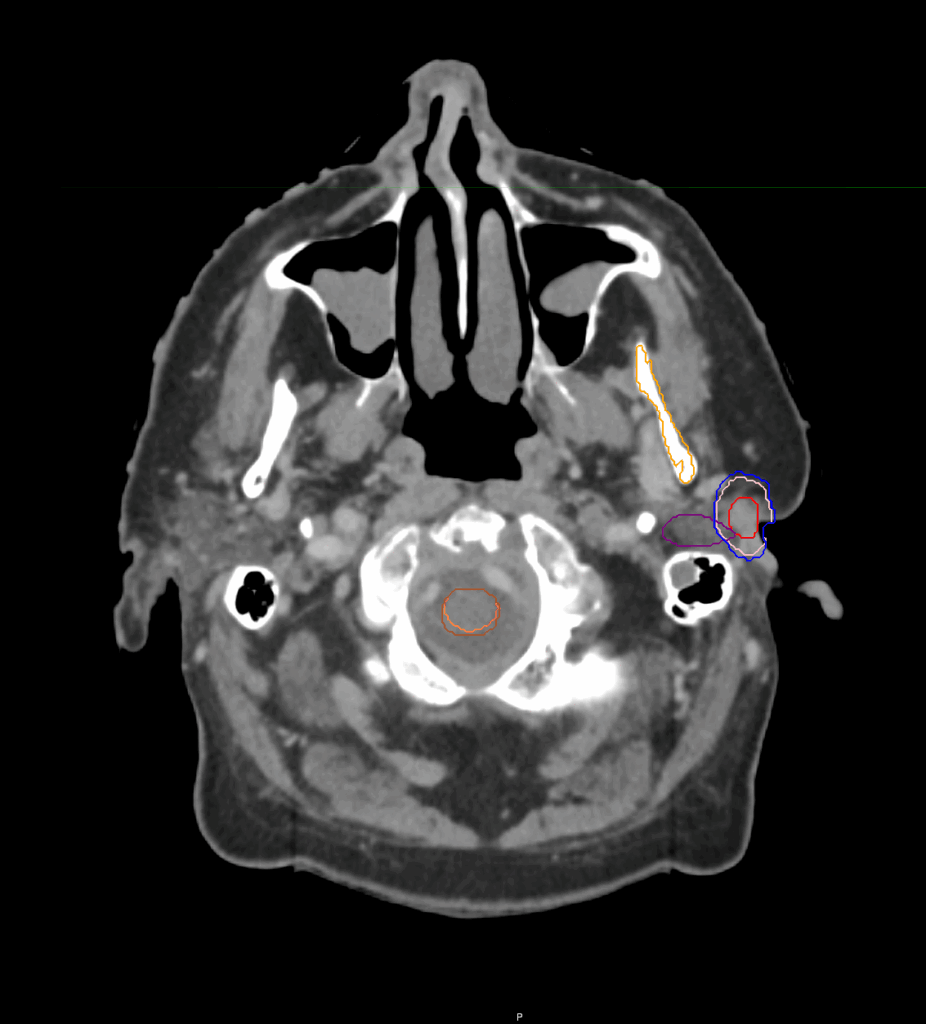

Planning CT Images